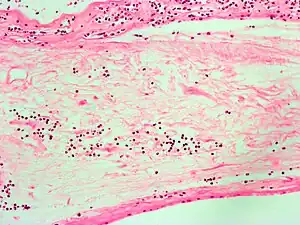

Corioamnionite é uma inflamação das membranas fetais (âmnio e córion), do liquido amniótico, placenta e/ou decíduas devido a uma infecção bacteriana. Tem mostrado-se de prevalência variável nos estudos, podendo acometer até 10% das gestações e até 40% dos casos de síndromes febris no trabalho de parto.[1] Geralmente resulta devido a bactérias que migraram ao útero através da vagina e está frequentemente associado a um trabalho de parto prolongado.